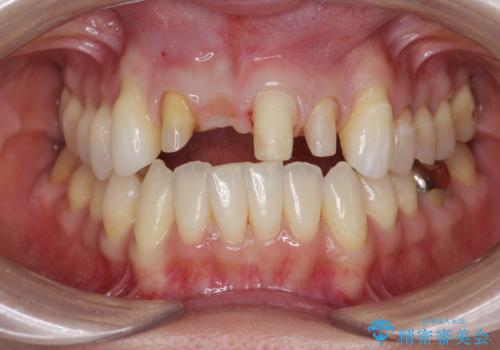

吸収し喪失した前歯、ブリッジによる審美性の回復

- 前医に前歯の吸収による抜歯の必要性を伝えられ、前歯の審美的な改善・治療を求めて来院されました。

CT撮影を行った結果、右上前歯は吸収が進み抜歯が必要な状態です、

抜歯をせず放置すると、より吸収が進み臨在する歯にも悪影響を及ぼしてしまう可能性が考えられます。

上顎4前歯は、根管治療の既往があり、虫歯も見られたことからブリッジによる治療で審美性の回復を行うとともに臨在歯の虫歯もセラミック治療を行っていきます。